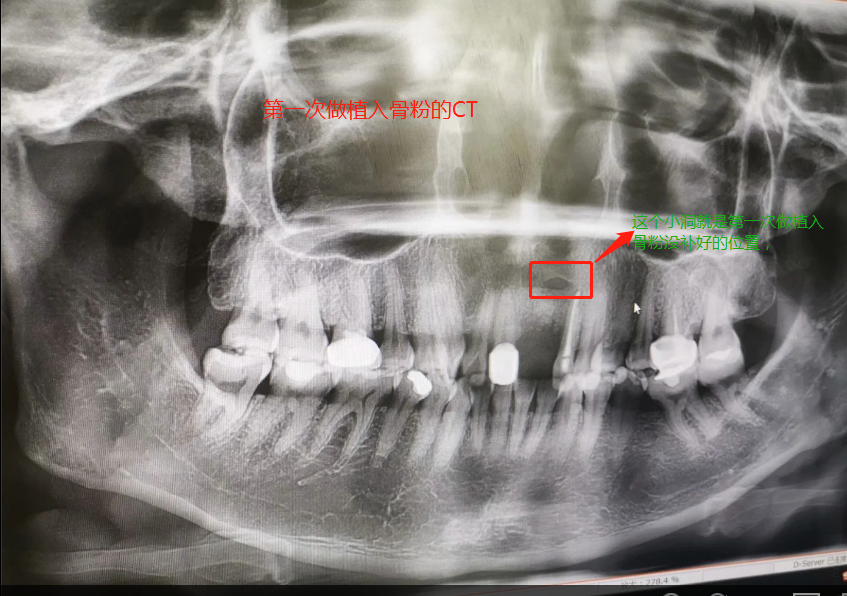

第一次做完植入手術(shù)后拍的CT

2019年7月27日做了種植骨粉手術(shù),在醫(yī)院要等半個(gè)小時(shí)留意一下是否有出血情況,沒有就可以回家休息。做手術(shù)是自己一個(gè)人坐地鐵來回的,勇敢吧。第一天嘴里都是血,第二第三天也是,臉也腫起來,也會(huì)有一點(diǎn)點(diǎn)骨粉掉出來,我那幾天都是喝粥和喝湯,第四天才敢吃飯,第七天傷口就好了,可以帶上臨時(shí)假牙,因?yàn)槲沂巧项€門牙,上顎骨頭密度沒有那么好,正常要等4個(gè)月左右,我的骨粉還是種植的,不是自身的骨頭,所以必須要等半年才能種種植牙。等到2020年1月26日去種植牙根的時(shí)候,那個(gè)主任已經(jīng)調(diào)去別的分店,第一次補(bǔ)完骨粉我就發(fā)覺里面還有個(gè)小洞,問醫(yī)生里面為什么有個(gè)洞的,醫(yī)生說沒事的。我打算去分店種植牙齒的,以為跟我那個(gè)醫(yī)生會(huì)比較了解我情況,后來那個(gè)的助理叫我不要去分店弄了,在這里安排個(gè)專家給我看。經(jīng)過專家的診斷,我還有個(gè)洞沒有補(bǔ)到骨粉,需要再做個(gè)補(bǔ)骨粉手術(shù)后等半年看看情況能不能種牙再說。我聽了真想哭起來,大門牙好不容易空半年可以種牙了,結(jié)果還要我補(bǔ)骨粉,還要等那么長時(shí)間。經(jīng)過跟這家醫(yī)院醫(yī)生溝通和別的門診醫(yī)生回答,決定還是回到這家醫(yī)院做修復(fù),跟助理談了價(jià)格,他說就收取800元,補(bǔ)0.5克骨粉。于是就開始了第二次手術(shù),第一次手術(shù)補(bǔ)了0.5克骨粉(2個(gè)單位,0.25克為一個(gè)單位),第二次補(bǔ)了0.75克骨粉,本來是0.5克骨粉,醫(yī)生做手術(shù)的時(shí)候說還有點(diǎn)間隙,還需要0.25克骨粉,問我要不要加,我說加,就算要另外收費(fèi),我也要加,我的牙齒受的折磨太多了。我要好好弄好這顆牙齒,就收了800元,也沒有額外收0.25克的骨粉錢。我在這家口腔醫(yī)院花了6800元種植骨粉,第二次骨粉植入傷口比較大,醫(yī)生說恢復(fù)期要12天,確實(shí)7天傷口還是沒有恢復(fù)的很好。而且今年1月底爆發(fā)疫情,1月31日領(lǐng)導(dǎo)就讓我們上班,我們公司是做醫(yī)療設(shè)備。傷口都沒有完全康復(fù)就堅(jiān)持上班了。